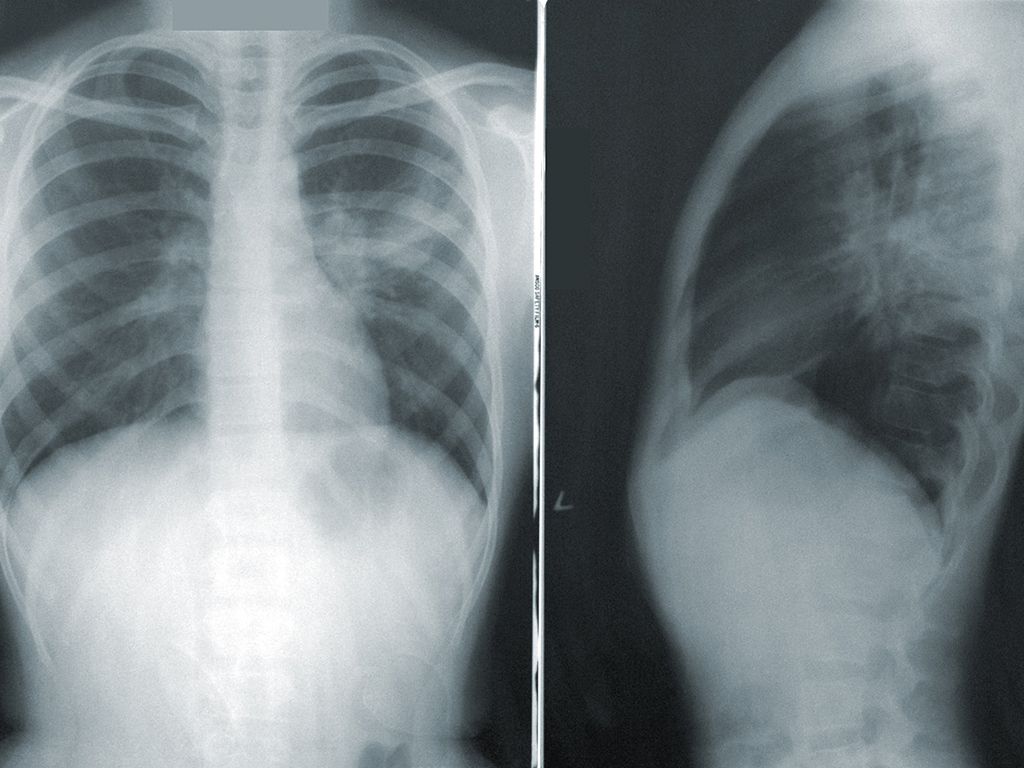

I’m not a medical professional, but my dad had a really serious cough and I told him he had to get it checked out. He ignored me for weeks and just kept coughing away. At some point, he started coughing up blood and I essentially forced him to go to the doctor.

He was diagnosed with tuberculosis which was scary enough, but then the doctor revealed an unsettling truth— if he had left it any longer, he would have been a goner. Most of the time he had the cough, he was overseas—he gets paid to work in places like India, China, Korea.

We FaceTime regularly, so luckily, I wasn’t around him very much for most of the duration of his cough (or presumably when he first caught it). It was maybe a day after he came home after being abroad that he coughed up blood.

I later found out that I guess I’m really lucky I wasn’t around him a lot, because I probably would have caught it otherwise.